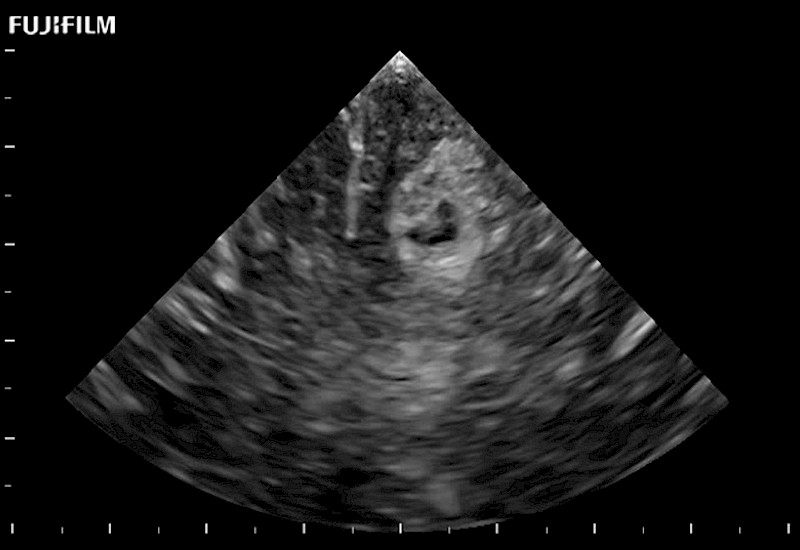

The world's only phased array burr-hole transducer that is ideal for scanning during burr-hole guidance procedures.

Main Specifications: